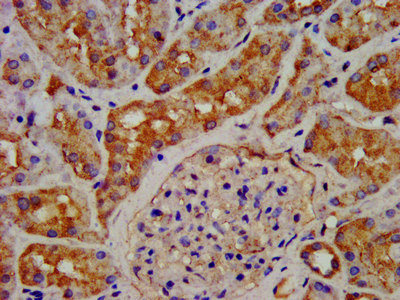

IHC image of CSB-PA009413LA01HU diluted at 1:200 and staining in paraffin-embedded human kidney tissue performed on a Leica BondTM system. After dewaxing and hydration, antigen retrieval was mediated by high pressure in a citrate buffer (pH 6.0). Section was blocked with 10% normal goat serum 30min at RT. Then primary antibody (1% BSA) was incubated at 4°C overnight. The primary is detected by a biotinylated secondary antibody and visualized using an HRP conjugated SP system.